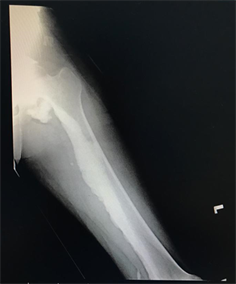

Figure 4. X-ray of left tibia/fibula (AP/lateral view) showing osteoma-like hyperostosis involving the long axis of tibia. Narrowing of medullary cavity is also observed here.

Conventional radiographic imaging such as plain X-ray is used to diagnosed melorheostosis, in which the typical melting wax dripping down a candle appearance may be seen, showing extensive, dense, irregular eccentric hyperostosis of both periosteal and endosteal surfaces of cortex resulting in deformity over bones and narrowing of marrow space. Both patients reported by Bruno et al. and Rakesh et al. has similar pathognomonic findings of “dripping candle wax” appearance in plain X-ray suggesting the diagnosis of melorheostosis [3] [6] . Freyschmidt described three additional patterns of radiological patterns:

1) “osteoma-like” hyperostosis involving only the endosteal surface, which orientates in the long axis of involved bone. Lesions may be 5 cm or larger in diameter, may involve more than one bone and eccentrically located. If only one bone involved, circumscribed scleroderma or subcutaneous fibrosis above the lesion may be seen [7] .

In our case study, plain imaging shows “osteoma-like” hyperostosis involving the endosteal surface along the long axis of femur and tibia. Calcium deposits can be observed over medial aspect of the femur. Proceeded with CT, which reported as undulating cortical hyperostosis at medial aspect of the femur and proximal tibia plateau with hyperostosis within medulla of proximal tibia and linear hyperdensity is seen between vastus medialis and sartorius with irregular calcium deposits seen at the medial aspect of medial femoral condyle, anterior knee joint and posterior knee joint.